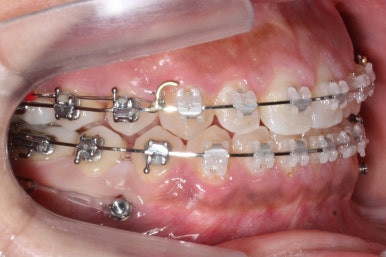

위 사진은 부산치아교정치과에 내원하셨을 대 당시의 입안 모습입니다.

치아들 사이에 전반적으로 틈이 많이 있는 상태입니다.

장치 부착 모습입니다.

이번에 부산치아교정치과에서 사용한 장치는 클리피씨라는 자가결찰 세라믹입니다.